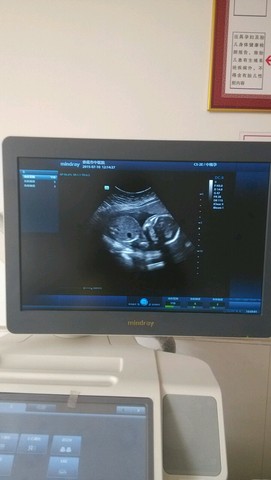

昨日超完回来,说胎盘位置低,可能是边缘性前置胎盘

不想剖腹,不想孕晚期担惊受怕,有同样情况的宝妈胎盘长上去了,平安顺产的吗?!?!![]()